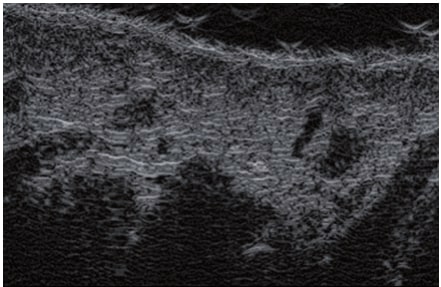

La sonographie Doppler permet l’imagerie des gros vaisseaux et des perforantes qui sont généralement situés dans les couches plus profondes du tissu sous-cutané (fig. 1). Malheureusement, la sonographie conventionnelle n’est pas capable d’imager les vaisseaux plus petits. Afin de visualiser les vaisseaux plus petits situés près de la surface de l’épiderme et dans la couche supérieure du tissu sous-cutané, l’EHF est utilisée (fig. 1). Grâce à l’utilisation de transducteurs dont les fréquences sont supérieures à 20 MHz, une image échographique à haute résolution est obtenue dans laquelle nous pouvons différencier des structures qui sont plus petites que 0,1 mm. Cependant, plus la résolution est élevée, moins la pénétration du faisceau ultrasonore dans les couches de la peau est profonde. Par conséquent, selon le transducteur et l’appareil, il est possible de pénétrer la peau jusqu’à une profondeur maximale de 20–30 mm. Une telle pénétration, associée à une haute résolution d’image, permet l’évaluation de vaisseaux sanguins même très petits (fig. 2). Pendant l’examen avec l’utilisation de transducteurs à haute fréquence, on peut évaluer avec précision le trajet et l’emplacement des petits vaisseaux dans la peau. Cela est particulièrement pertinent pour la sélection de la méthode de fermeture des vaisseaux et la planification de la procédure, car en pratique, la surface de la peau ne montre très souvent qu’un petit nombre de vaisseaux ou un léger fragment de vaisseau – ce n’est qu’après l’examen US que nous pouvons déterminer leur nombre réel et leur trajet. Pour une fermeture efficace du vaisseau, il est nécessaire de le faire sur toute sa longueur. Elle ne doit pas se limiter au fragment vu « à l’œil nu » à la surface de la peau, car la fermeture du fragment entraînera sa recanalisation rapide(7). Fréquemment, le vaisseau visible à la surface de la peau change de trajet, devient plus tortueux et se déplace vers les couches plus profondes de la peau(8). Par conséquent, le trajet de la veine et des perforantes doit être bien connu et déterminé avant la procédure. L’EHF permet également l’imagerie des perforantes entre les petits vaisseaux. De plus, outre l’évaluation du trajet et de l’anatomie, l’image échographique, grâce au logiciel d’échographie, permet également de déterminer les paramètres de base tels que le diamètre du vaisseau, l’épaisseur de sa paroi, la profondeur dans la peau ainsi que la présence ou l’absence de perfusion à l’intérieur du vaisseau(6) (fig. 3). Grâce au transducteur électronique multi-éléments d’une fréquence de 40 MHz introduit sur le marché par Ultrasonix, il est également possible de visualiser la perfusion des vaisseaux en mode Doppler couleur (fig. 4).